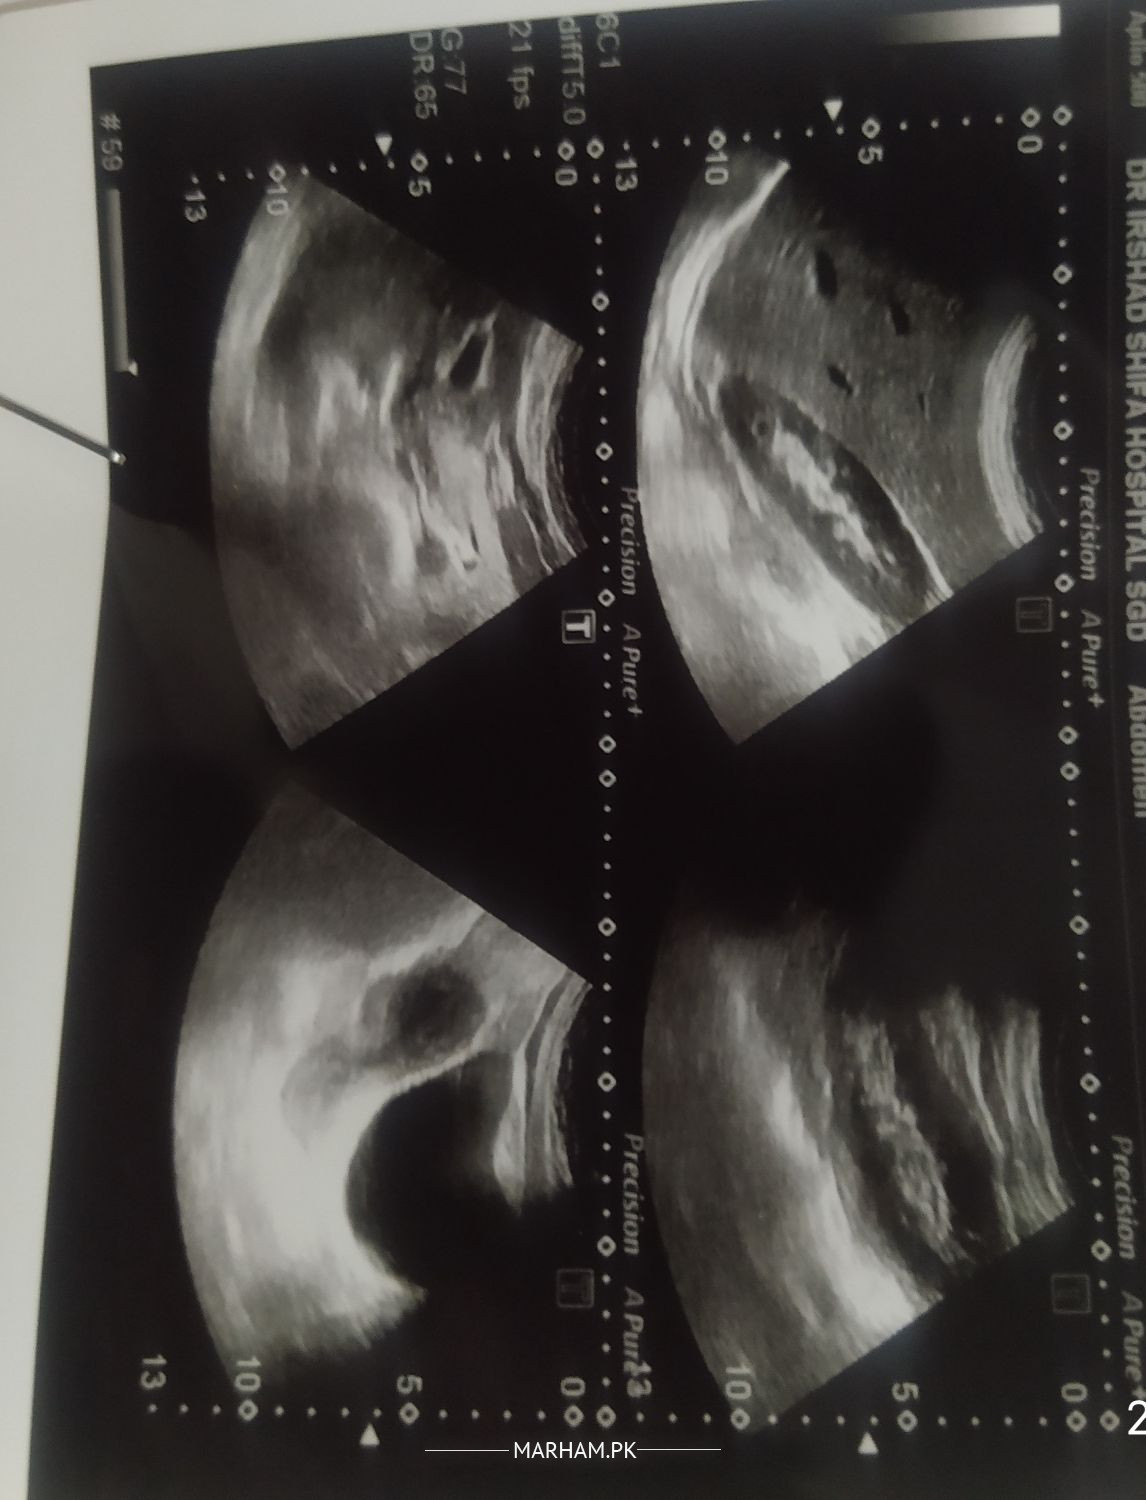

Asking For Wife, Female 30, sargodha

A.O.A Dr please see reports and suggest what to do, please.

Appendices Hai pr clinical diagnosis is more important visit a surgeons

Attach Photo here: